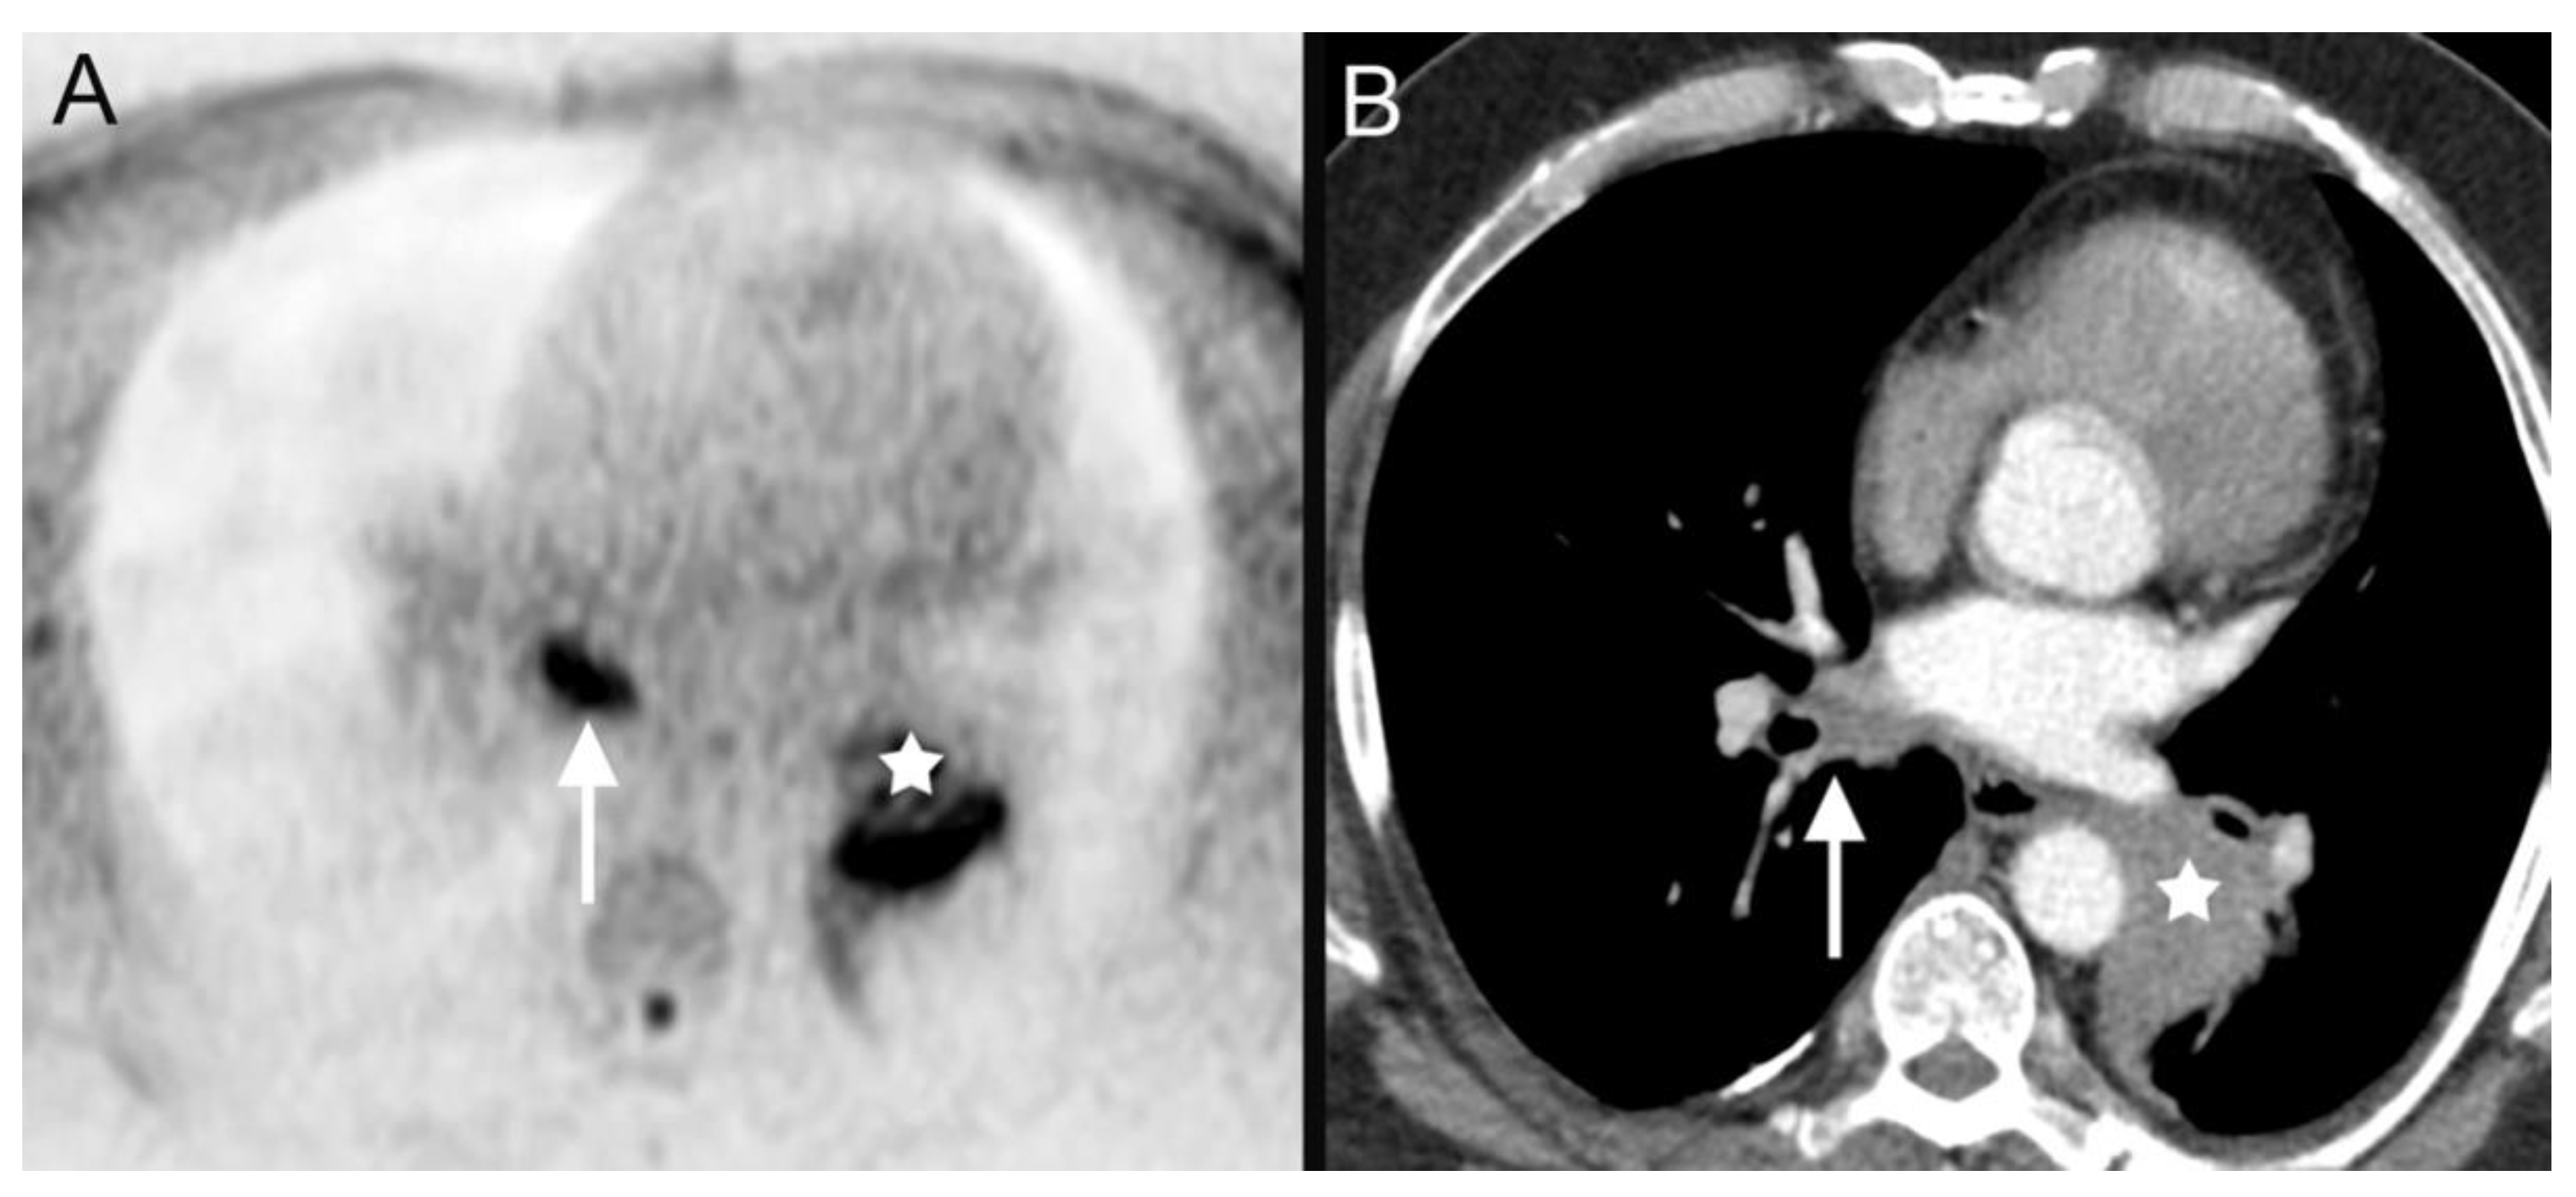

| 18 | leukemia (Figure 5) | ||